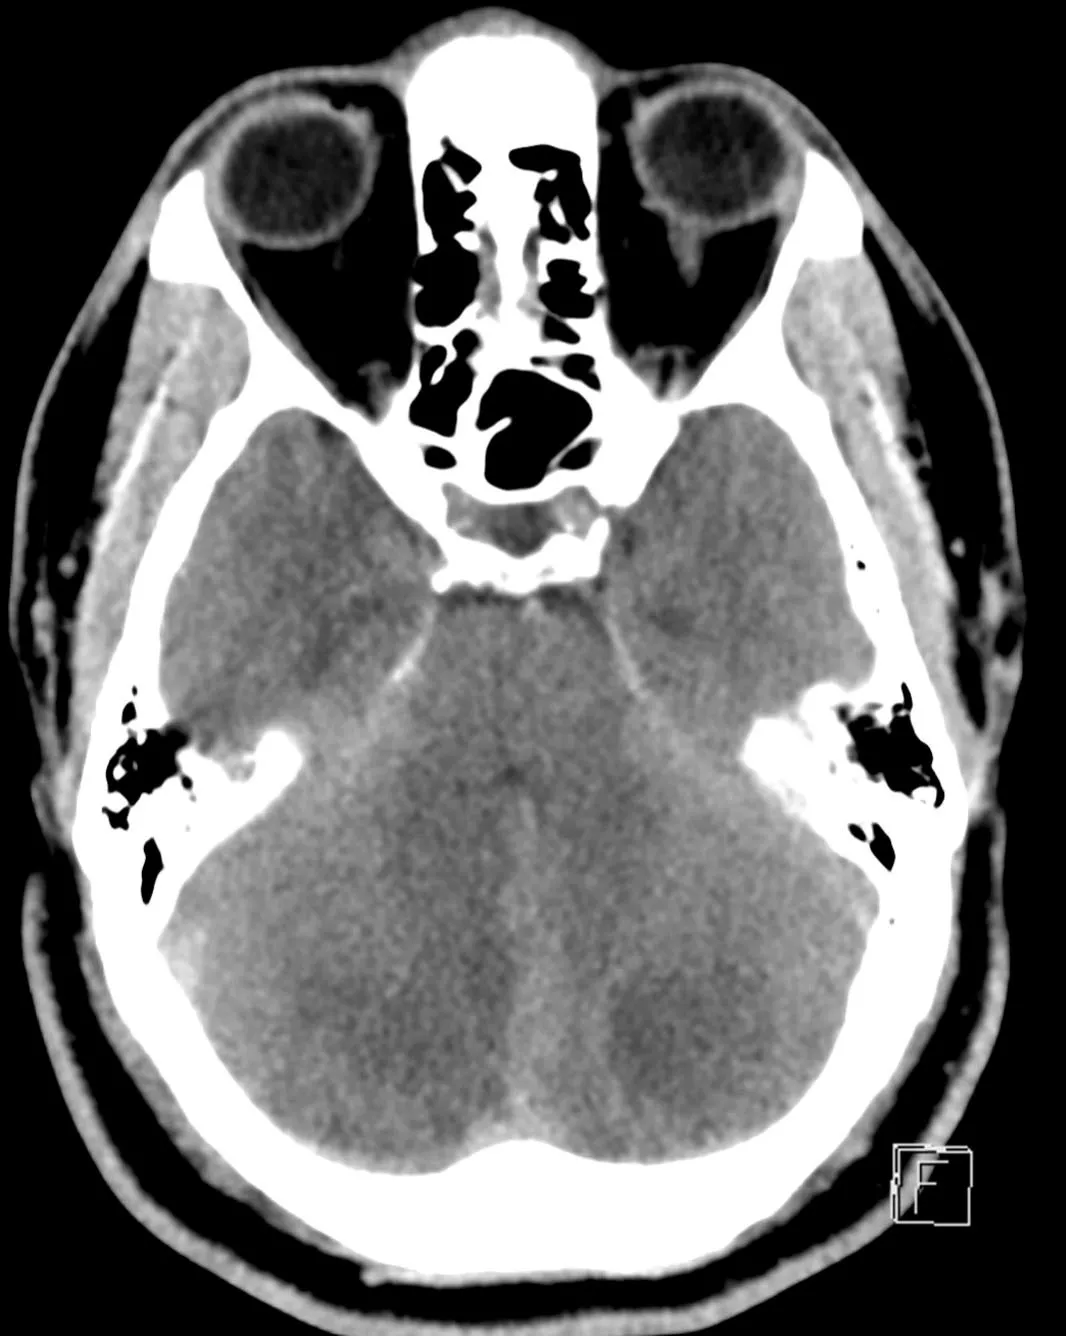

Approximately 12 hours after admission, the patient experienced a decline in his mental status, prompting a stat non-contrast computed tomography (CT) of the head which revealed bilateral cerebellar strokes. The associated cytotoxic edema resulted in significant mass effect on the 4th ventricle and early hydrocephalus.

The patient was then taken to surgery for an emergency sub-occipital decompressive craniotomy and placement of an extra ventricular drain to relieve the pressure.